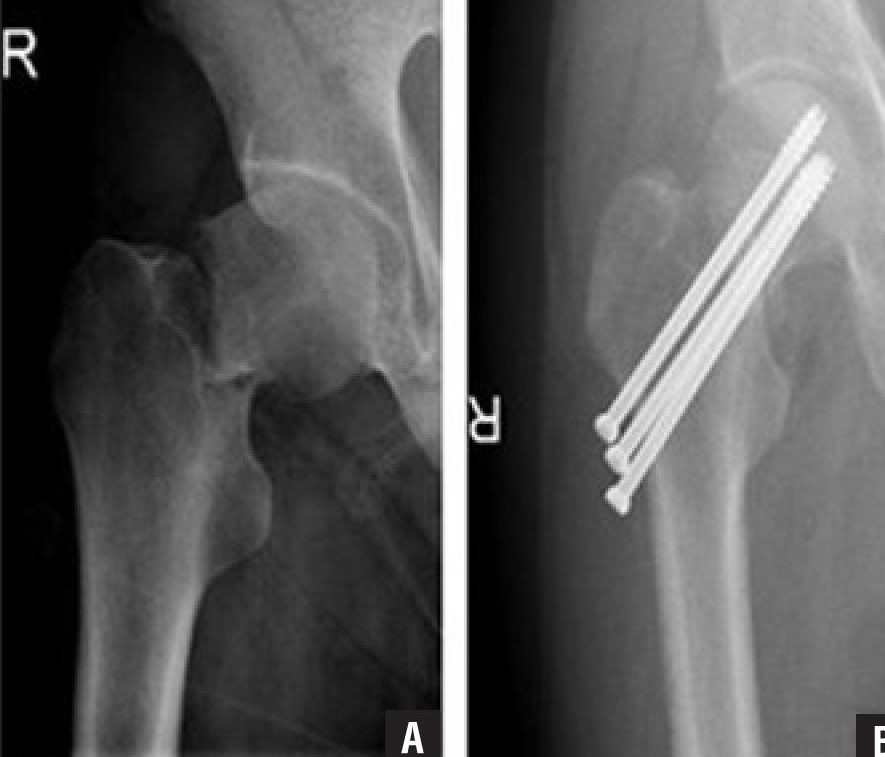

Upload Date: March 31, 2019 Full Size Image Dimensions: 885 × 757 Image Parent Post: Κατάγματα κάτω άκρου

1.Ήλωση κατάγματος μηριαίας κεφαλής με κοχλίες